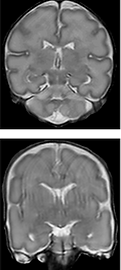

A prerequisite to quantify brain development is to segment MRI into different brain tissue types. It's simply possible to manually go over every single slice of MRI and paint the brain into different tissue types, such as cortex, white matter, and gray matter. This job is categorized as one of the most boring jobs and it's extremely time-consuming. And here is where my research make sense, to develop an automatic algorithm to quantify brain development using machine learning and deep learning. The results of this research are published in AI special issue of MRI journal and ca be find here.

Recently, machine learning methods and particularly deep learning achieved excellent performance in many tasks. Many technologies from autonomous driving to face detection available in smartphone cameras are using these algorithms. Convolutional neural networks (CNNs) is the most popular network in image processing, classification, and segmentation tasks. This network shows high performance in medical image segmentation. However, the results are optimal in scans with artifacts (see the second column of the above figure). These scans visualize motion artifacts that are occurring due to infants' movement during the scanning. To overcome this challenge, an algorithm using another type of neural network recently widely used in image generation called generative adversarial network (GAN) is used. GAN composed of two networks, a generator, and a discriminator. We used this algorithm to remove motion artifacts from scans and improve brain tissue segmentation simultaneously. The results are published in MICCAI 2019 and can be find here.